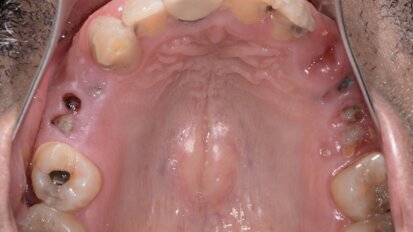

Motivated by his desire to simplify the treatment process for patients, Dr Philip Tan has developed a full-arch implant-retained prosthesis for completely ...